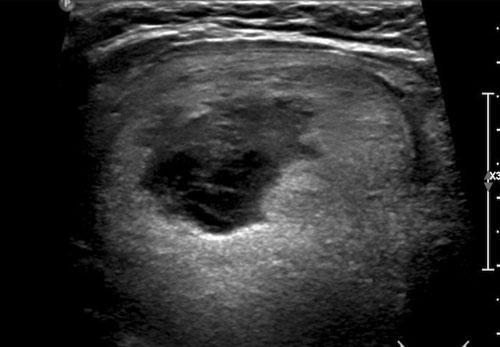

Trường hợp 3

Quan sát hình ảnh và xác định điểm TI-RADS.

Cuộn hình ảnh để xem điểm TI-RADS.

Lưu ý các tiêu điểm tăng âm nhỏ hiện diện.

Tổng cộng 6 điểm tương ứng với điểm TI-RADS là 4.